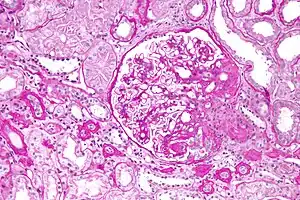

Light micrograph of focal segmental glomerulosclerosis, hilar variant. Kidney biopsy. PAS stain.

Word origin

The individual components of the name refer to the appearance of the kidney tissue on biopsy: focal—only some of the glomeruli are involved (as opposed to diffuse), segmental—only part of each glomerulus is involved (as opposed to global),[19] glomerulosclerosis—refers to scarring of the glomerulus (a part of the nephron (the functional unit of the kidney)). The glomerulosclerosis is usually indicated by heavy PAS staining and findings of immunoglobulin M (IgM) and C3-convertase (C3) in the sclerotic segment.[20]